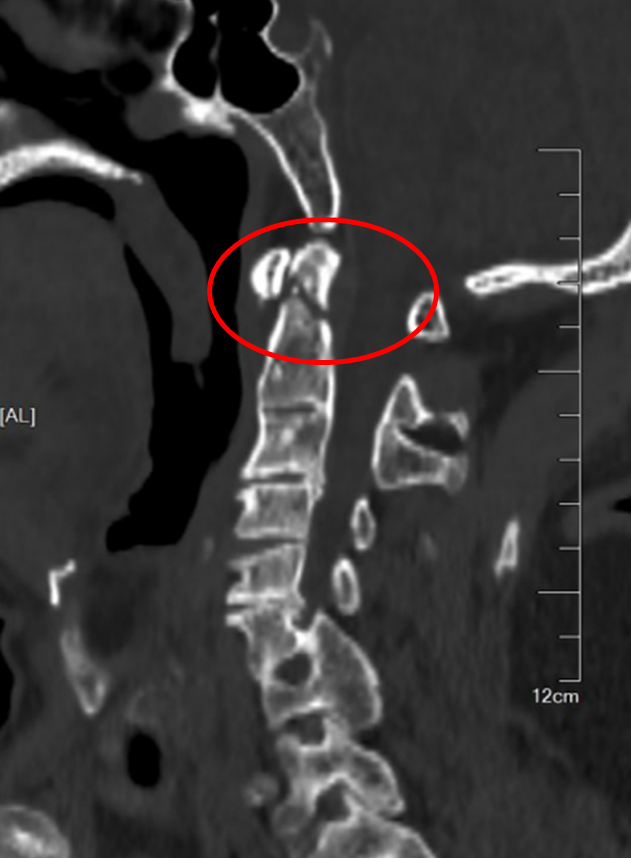

在麻醉手术科的严密监护下,刘义杰副主任医师首先熟练地完成了颈椎前路C3-4减压融合术(ACDF),成功解除了脊髓的压迫。然而,通过同一个仅3厘米的微小切口,精准地将螺钉植入游离且向后倾倒的齿状突具有极大的挑战性。关键时刻,骨科手术机器人发挥了“超级助手”的作用。团队利用机器人导航系统,对进钉点和角度进行了反复测算与调整,导针精准抵达目标。随后,由姜为民主任专利研发的一枚新型齿状突螺钉顺着通道顺利旋入,牢牢锁住了骨折端。整个过程出血量少,手术顺利完成。

图2:术后正侧位片